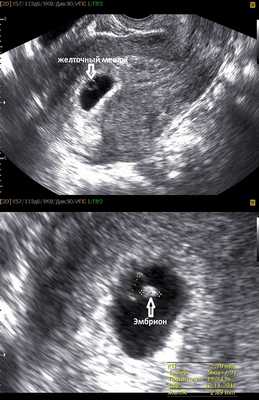

Фото УЗИ плода при беременности 5-6 недель

На этом сроке внутри плодного яйца появляется белое колечко - это желточный мешок.

Нормальные размеры желточного мешка 2-6 мм. Если в плодном яйце визуализируются два желточных мешка, значит это монохориальная многоплодная беременность. Но если внутри плодного яйца виден один желточный мешок, а эмбрион ещё отчётливо не визуализируется, то это всё ещё может оказаться монохориальная моноамниотическая двойня.

Эмбрион в начале 5-й недели практически неразличим на стенке желточного мешка, но уже к концу недели копчико-теменной размер (КТР) эмбриона достигает 3 мм.

СВД плодного яйца 11-16 мм.